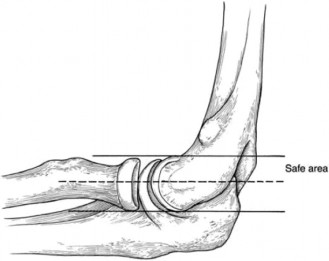

Appreciate that the outcome of calcific tendonitis is typically favorable with conservative measures? CASE 31 Dr. Robert J. Stewart A 29-year-old, left-hand-dominant male presents to clinic complaining of left arm and shoulder pain for the last three days. The patient is an avid weight-lifter and was doing the bench press when his arm began to bother him. He has been using ice and resting with mild relief but has not been able to use his left arm for anything more than carrying light-weight objects. He is also having difficulty with simple activities such as putting on his shirt. On physical examination, the patient has ecchymosis and a prominent cord-like structure on the anterior left axilla. He has significant weakness with left shoulder adduction and internal rotation. He has a negative Hawkins sign and a negative Yergason sign.

The correct answer is (B). A pectoralis major muscle (PMM) tear or rupture usually occurs in weight-lifters while performing the bench press, but it can occur during

any activity in which the arm is extended and externally rotated while under maximal contraction (eccentric loading force). Patients often present with pain, swelling, ecchymosis, weakness and loss of the axillary fold in the acute setting. In the chronic setting, the swelling and ecchymosis have typically subsided. They may report an audible pop or a tearing sensation. On examination, there can be an apparent continuous muscle or tendon that is mistaken for an intact PMM tendon, but this represents the fascia of the PMM that is continuous with the fascia of both the brachium and the medial antebrachial septum. This continuous fascia will examine as a cord-like structure as shown in Figure 2–78.

Figure 2–78

The sternocostal portion of the muscle is injured more often than the clavicular. A rotator cuff tear and biceps tendon injury are unlikely given the mechanism of injury and physical examination findings. In addition, this patient is young for a rotator cuff tear. Poland syndrome is the congenital absence of the PMM. Pectoralis minor muscle rupture is scarcely reported and would not have the same history and physical examination findings.